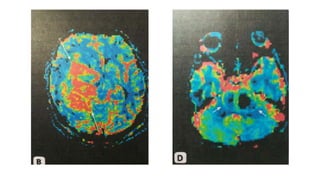

• Basic colors can tell the observer how the

fibers are oriented in a 3D coordinate

system, this is termed an "anisotropic

map". The software could encode the

colors in this way:

• Red indicates directions in the X axis: right

to left or left to right.

• Green indicates directions in

the Y axis: posterior to anterior or

from anterior to posterior.

• Blue indicates directions in the Z axis: foot-

to-head direction or vice versa.